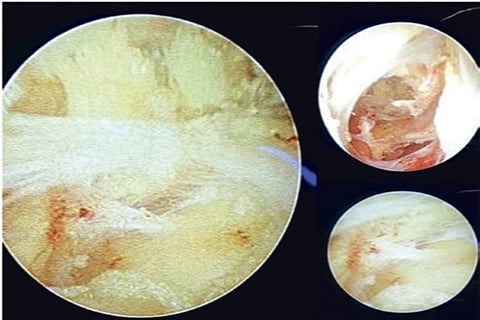

With these in mind, the surgeon at the SRM Medical College Hospital and Research Centre (SRM MCH and RC) in Kattankulathur have attempted to do a Video Assisted Anal Fistula Treatment (VAAFT) for patients.This novel technique, developed in 2006, is gaining popularity all around the world. SRM’s first patient was a 25-year-old male who came to the OPD with complaints of perianal discharge. Investigations were done which confirmed the diagnosis of fistula-in-ano. He was successfully treated with VAAFT and was discharged the next day as he had minimal post-operative pain, there was no open wound and there were no major complaints.

“We have so far done five cases of VAAFT with a high level of patient satisfaction,” said Pro Vice-Chancellor of Medical and Health Sciences Lt Col Dr A Ravikumar.